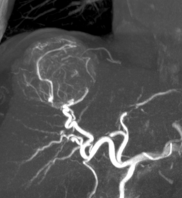

Module 1 : Foie et voies biliaires

- Pathologies hépatiques vasculaires – cas cliniques – niveau avancé

- Comment j’utilise les produits de contraste hépatospécifiques ? - niveau avancé

- Echographie de contraste hépatique

Module 6 : Radiologie interventionnelle

Indications des traitements radiologiques des tumeurs hépatiques sur cirrhose- Indications des traitements radiologiques des métastases hépatiques

- Indications et suivi des traitements radiologiques de l’HIP et de la thrombose portale